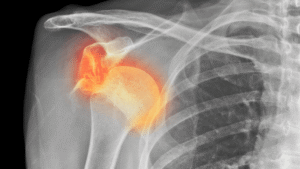

A Bankart lesion is a tear of the shoulder labrum that occurs when the shoulder dislocates.

The labrum is a ring of soft tissue around the socket of the shoulder joint (glenoid) that helps keep the ball of the arm bone in place.

When this ring is torn, the shoulder becomes unstable and may dislocate again, even with small movements.

Diagnosis is based on clinical examination and MRI of the shoulder.

MRI findings typically show:

- Bankart lesion (labrum tear)

- Hill–Sachs lesion on the humeral head

- Sometimes a Bony Bankart if a bone fragment is involved